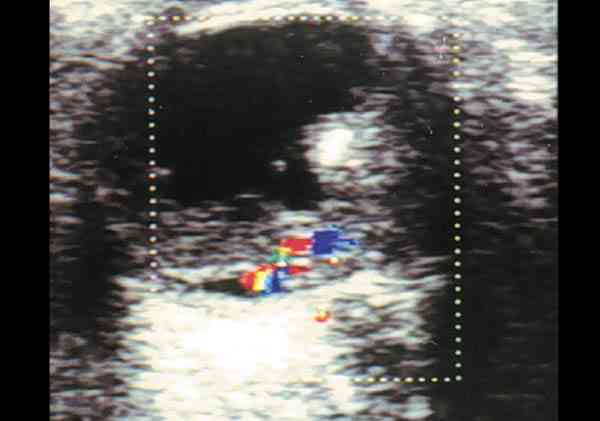

Figura 3. Retinoblastoma vascularizado mediante el doppler color se

observa el registro correspondiente a un vaso arterial.